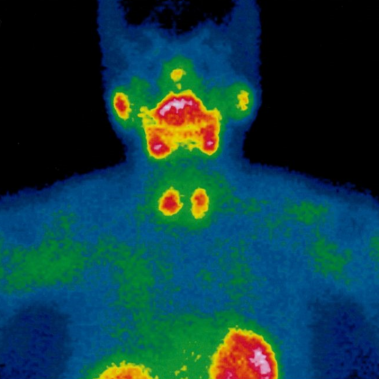

Cenedyt Servicio de Medicina Nuclear se creó hace más de 20 años. Las técnicas de imagen han tenido un desarrollo espectacular en los últimos años y cada vez juegan un papel más relevante en el proceso diagnóstico y terapéutico de los pacientes. El número de exploraciones realizadas es cada vez más elevado.

Estamos especializados en Medicina Nuclear y Densitometría. Nuestro objetivo y ofrecer al paciente la máxima calidad en Diagnóstico y tratamiento, basándonos en nuestra amplia experiencia y últimas tecnologías.